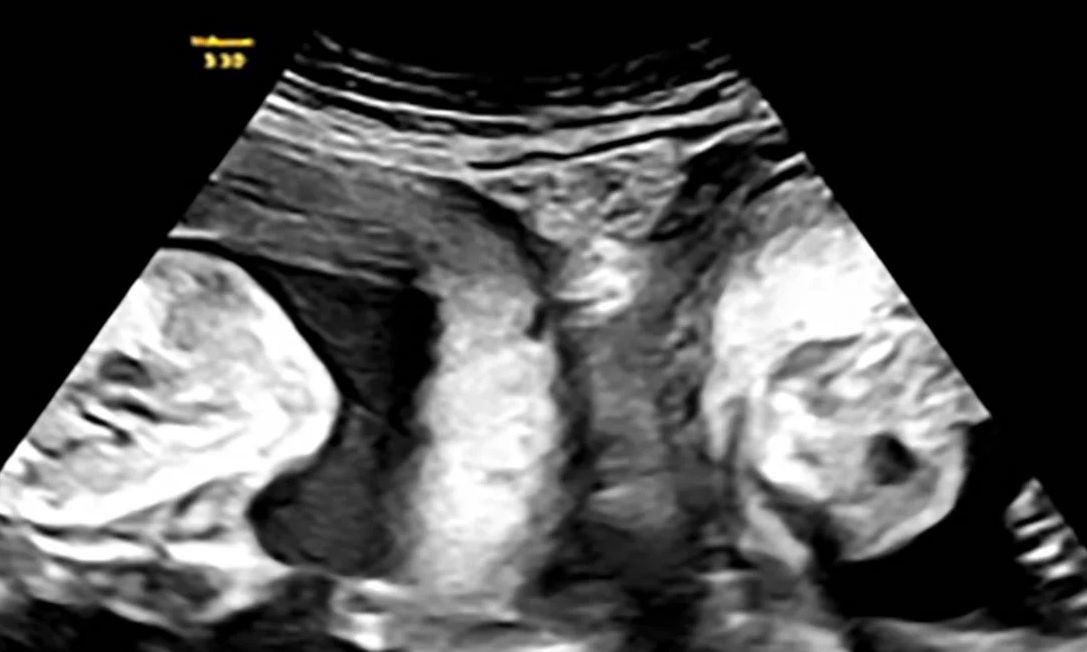

Αλλά τον Ιανουάριο, η Li έμεινε ξανά έγκυος και ανακάλυψε κατά τη διάρκεια ενός πρώιμου υπερηχογραφήματος ότι δεν περίμενε μόνο ένα παιδί αλλά δίδυμα – ένα σε κάθε μήτρα.